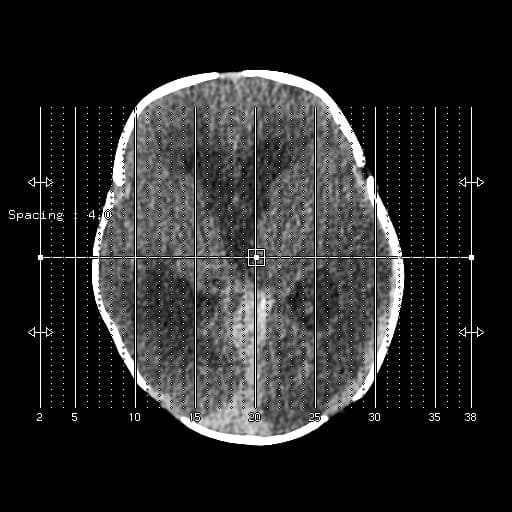

Axial DWI

- Hạn chế khuếch tán (restricted diffusion) lan tỏa ở chất trắng vùng trên lều tiểu não, tương ứng với các vùng tăng tín hiệu trên hình ảnh FLAIR.

- Ngoài ra, có các vùng tăng tín hiệu trên FLAIR ở dải vỏ não (cortical ribbon) và các nhân nền (basal ganglia) hai bên, với hạn chế khuếch tán tương ứng nhẹ ở vùng vỏ quanh vận động (peri-rolandic cortex).

Xét theo tiền sử bệnh lý, các phát hiện hình ảnh này phù hợp với bệnh lý thoái hóa trắng sau thiếu oxy chậm (delayed posthypoxic leukoencephalopathy) sau tổn thương não do thiếu oxy-thiếu máu (hypoxic-ischemic encephalopathy).